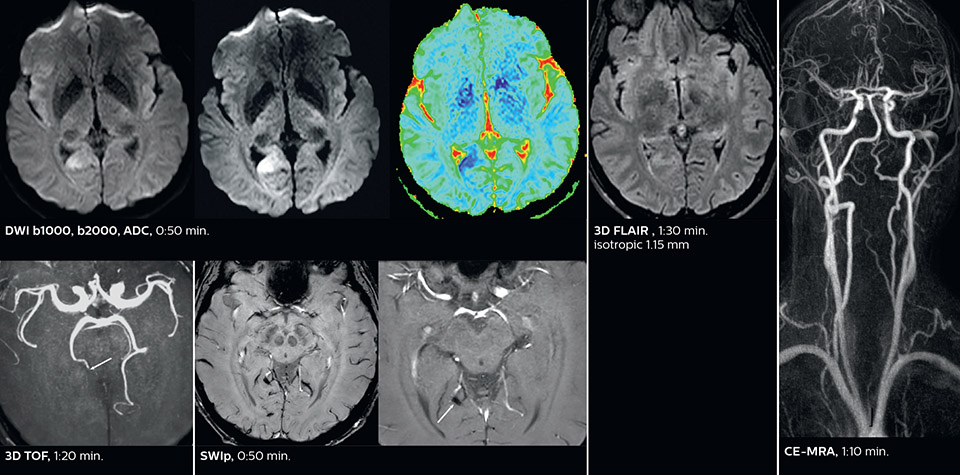

According to Dr. Savatovsky, Ingenia Elition has an impact in virtually all examinations. “We can either make the scanning faster compared to our older Ingenia 3.0T, or we save enough time so that we can add sequences we wouldn’t perform otherwise, or increase resolution. So, I think it has benefits for most of our patients.” “Some routine exams that we use every day have been shortened since we started using Elition. For example, we now use mostly a comprehensive stroke protocol (high b-value diffusion, fast 3D FLAIR, TOF, supra-aortic vessels angiography, SWIp, T1 post gad) that lasts 10 to 11 minutes, but our fast stroke protocol takes only 7 minutes. Our routine IAC needs about 10 minutes scan time and our comprehensive brain MS examination requires no longer than 13 minutes of scan time. Our ability to reduce acquisition times of most sequences helps to shorten total examination times, which in turn helps us to increase the number of patients we scan per day. “The main breakthrough for us was that Compressed SENSE and Multiband SENSE have allowed us to accelerate our examinations. Alternatively, we can invest the time gained in obtaining higher spatial resolution to see more details, or we can add additional sequences,” says Dr. Savatovsky. “That’s a big improvement from what we did before.”

The MRI center at Fondation Rothschild receives several neuro and head/neck emergency cases per day. On weekdays, an average of 7 unscheduled patients will require scanning, with approximately 4 to 5 patients actually requiring an urgent MRI scan, according to Dr. Savatovsky. He notes that the ability to accelerate sequences while maintaining image quality is particularly important in the emergency setting. “The fast scanning capabilities that came with Elition allow us to do a really quick examination and answer a lot of questions within a short time. We use every tool available to accelerate image acquisition while maintaining a reasonable image quality. So, for most of the sequences we use Compressed SENSE, for example, in our 3D FLAIR, in contrast-enhanced and noncontrast MR angiography, and for susceptibility-weighted sequences.” Among the emergencies that are routed to the MRI department at Fondation Rothschild, stroke is seen almost daily. “After arriving, acute stroke patients are immediately brought to the MRI preparation room and positioned on the FlexTrak table. There, the neurologist examines the patient and the biological workup is performed. Once this is finished, we can immediately move the patient with FlexTrak into the MRI and begin the scanning within one or two minutes. So, having the FlexTrak is a big advantage for us.”

Dr. Savatovsky appreciates the improvements and flexibility that Elition with Compressed SENSE and MultiBand SENSE provides, particularly for stroke patients. “For stroke, it allows us to cut about 5 minutes off of our stroke protocol, or to keep the same acquisition time and get more insights.” The ability to perform more sequences can help in making a swift and confident diagnosis. “For example, our stroke cases usually include the regular sequences that every center does (b1000 diffusion, FLAIR, time-of-flight angiography), but we also image supra aortic vessels, and we can replace a gradient echo sequence with a fast 50-second susceptibility-weighted sequence, and all of this doesn’t add much time. because all the regular sequences are accelerated on Elition.” “The time savings with Compressed SENSE and MultiBand SENSE make it easier to add sequences to give us additional insights. Depending on the context and the first results, we might add a DSC perfusion to assess the ischemic penumbra, an ASL perfusion to help find an alternative cause in case of normal diffusion, or add a high-resolution T1 sequence for a stroke patient, to quickly assess wall imaging in emergency cases. The additional sequences can help improve patient management, because we can already consider some alternative diagnoses if the morphological MRI is normal.”

This is an example of acute ischemic stroke with distal occlusion of the right posterior cerebral artery. Note the improved visibility of the ischemic territory on the diffusion weighted image with high b-value. The 3D FLAIR shows a distal PCA occlusion. The fast SWIp depicts the thrombus on the isolated second echo image. The total scan time (including SmartBrain, preparations and a fast 3D T1w TSE Gd) is 8:00 minutes.